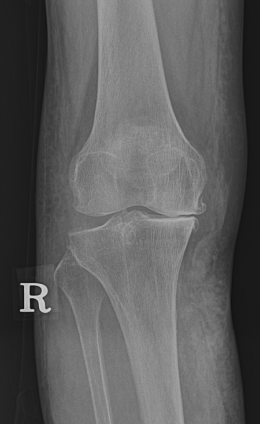

수술 전후 사례

-

수술 전

수술 후